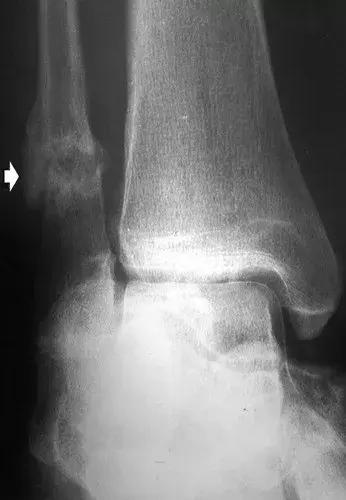

图17:42岁男性糖尿病人,踝关节和后足的神经性骨关节病。侧位X线片显示胫骨远端破坏吸收,并且具有类似于手术截肢的尖锐边缘。 距骨圆顶被吸收。 存在硬化,并且不再能够识别距下关节(箭头)。